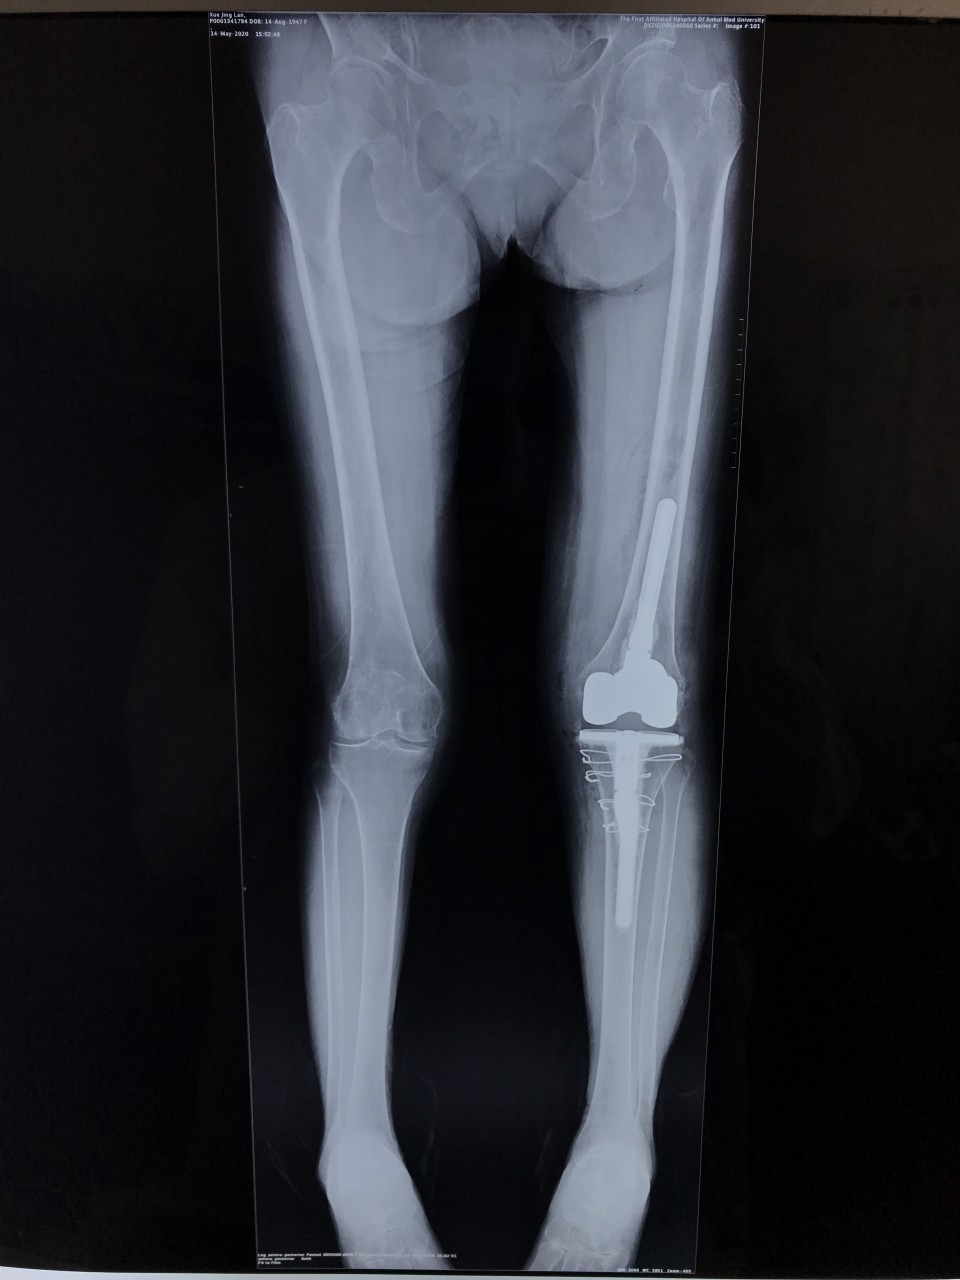

5月11日,一位72岁女性患者因“双膝关节疼痛伴活动受限8年,加重半年”入院,术前摄片提示双侧膝关节骨性关节炎。左侧膝关节伸直型僵直,屈伸活动度范围为0°。 我科胡孔足主任术前结合患者病史,体检及辅助检查,制定详实方案,先行左侧全膝关节置换术,术中采用TTO(胫骨结节截骨术),患者术后第二天下地正常行走,5月18日出院时已经能够完全自主抬腿,膝关节屈曲可达100°,减轻了患者的疼痛,明显提高了生活质量,疗效满意。